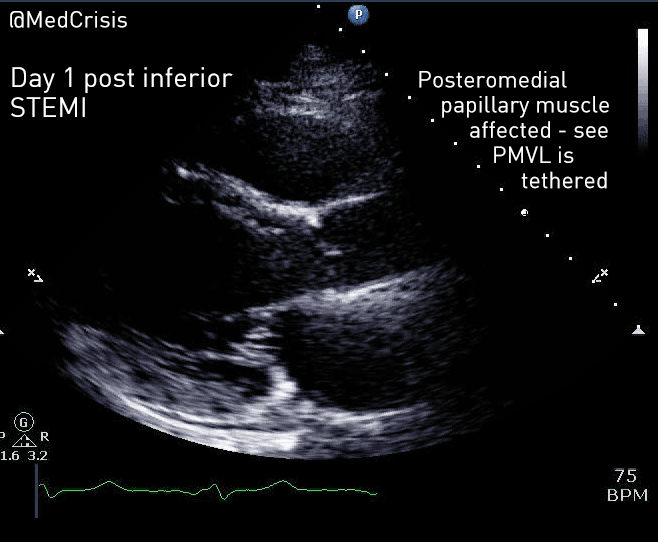

A bedside echocardiogram was performed.

A parasternal long axis view reveals the posterior mitral valve leaflet is tethered. The basal posterolateral wall is hypokinetic.

The anterolateral papillary muscle is connected to the anterior mitral valve leaflet and receives a blood supply from both the left anterior descending artery (via a diagonal) and the circumflex artery (via an obtuse marginal). However the posteromedial papillary muscle only has one blood supply, which is the posterior descending artery, a branch of the right coronary artery in 90% of people.

Therefore one can appreciate why mitral valve problems are more common following an inferior STEMI. In this case an almost akinetic segment, which included the posteromedial papillary muscle, caused the posterior mitral valve leaflet to become fixed, causing mitral regurgitation. Even though overall left ventricular function was only mildly impaired on the echocardiogram, the regurgitant pressure into the lungs can precipitate pulmonary oedema.